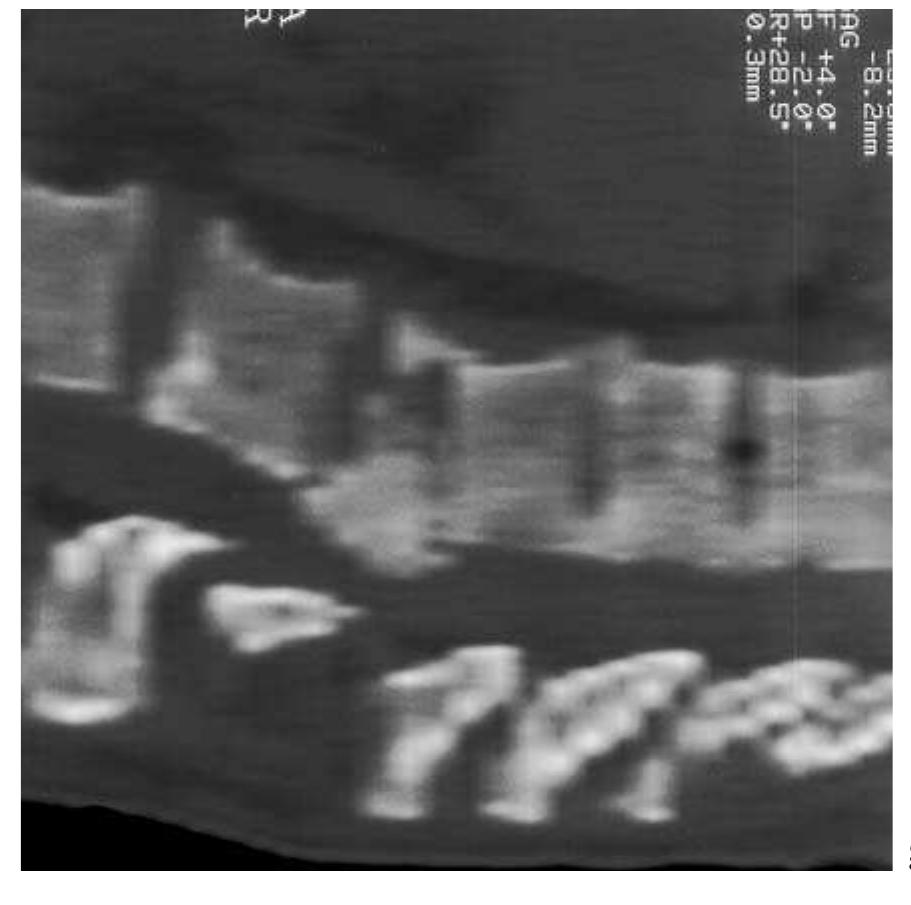

![Fig. 5.26 - Osteoblastoma of the posterior arch of C5. The MRI examination reveals a hypointense lesion within the posterior arch of C5 on the right. The CT study shows a sclerotic mass lesion of the posterior arch of C5. [a) oblique-sagittal T1- weighted MRI; b) axial T1-weighted MRI; c) axial CT].](https://figures.academia-assets.com/35610716/figure_402.jpg)